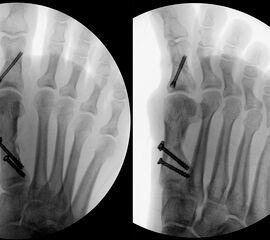

• Gute Stabilität durch Stabilisierung mit einer oder zwei perkutanen Schrauben möglich.

• Die Operationsplanung erfolgt anhand der Röntgenaufnahmen des Vorfußes unter Belastung in 2 Ebenen. Für die Verfahrenswahl sind wichtig der Intermetatarsalwinkel und die Breite des Os metatarsale, der Hallux valgus Winkel, der distalen Gelenkflächenwinkels (Distal Metatarsal Articular Angulation - DMAA), des Metatarsaleindex und Sesambeinposition (Abb. 1).

• Kanülierte Schrauben bis 50 mm Länge, 4 mm Durchmesser, Beilagscheiben.

• Röntgenkontrollen (Vorfuß d.p. und seitlich) postoperativ ohne Belastung. Weitere Kontrollen erfolgen 6 Wochen, sowie 3, 6 und 12 Monate jeweils unter Belastung.

• Bruch der medialen Kortikalisbrücke mit Verkürzung und Elevation des 1. Strahles. In diesem Fall muß die Länge des 1.Strahles durch eine quer zur Schaftachse plazierten Schraube gesichert werden. Als Alternative bietet sich eine lange Schraube durch den Schaft als intramedullärer Kraftträger an